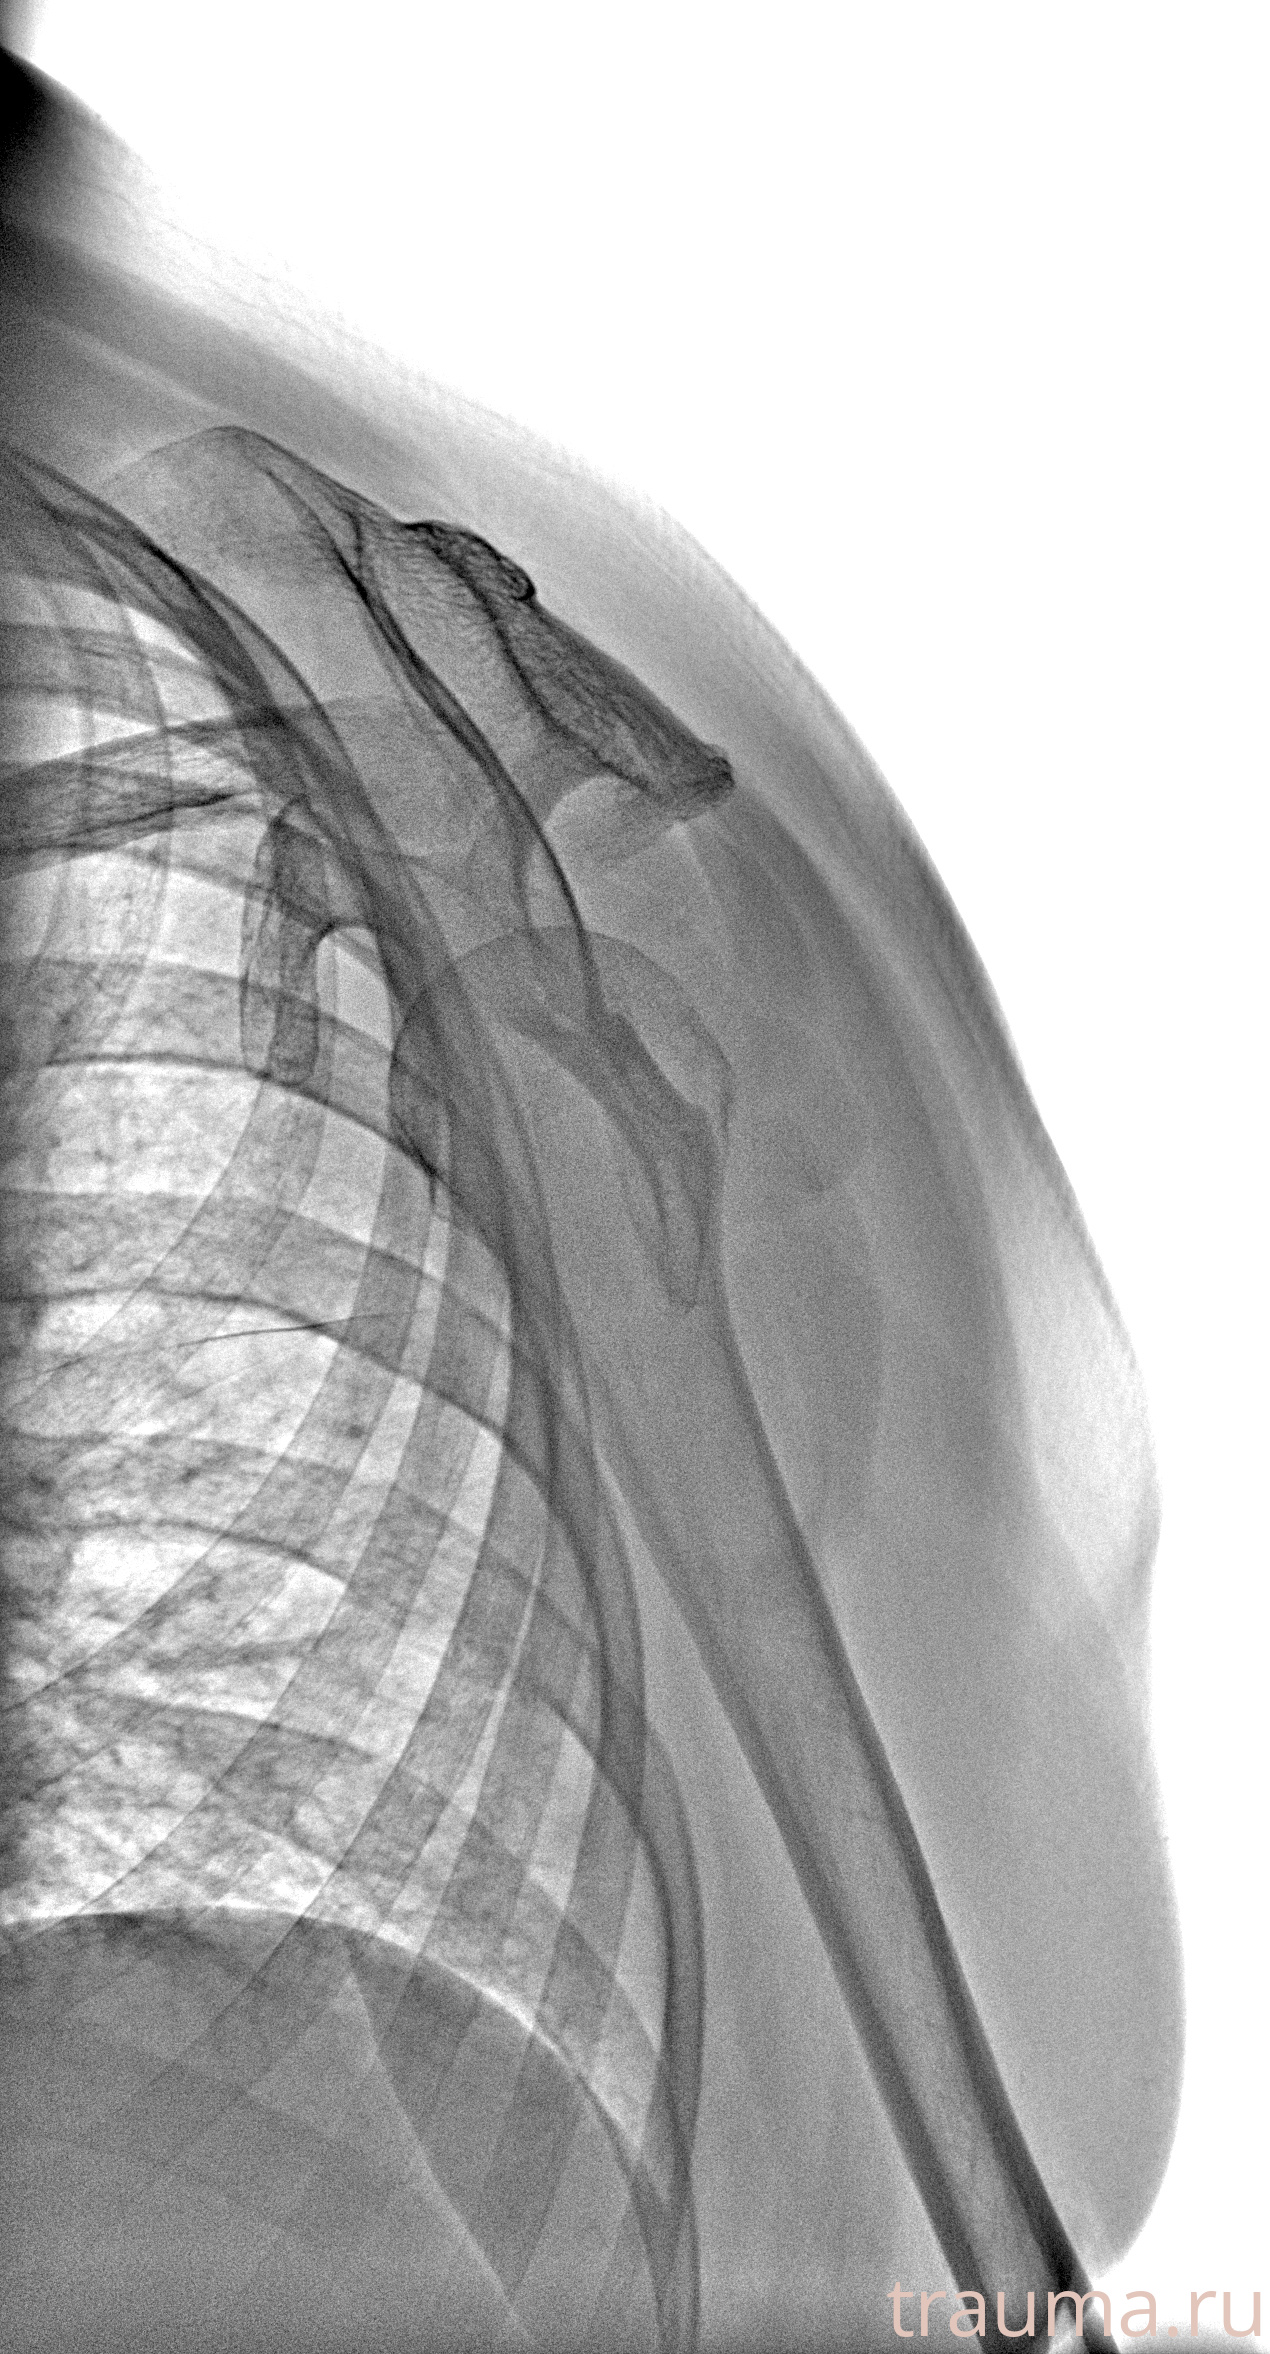

Рентгенограммы

Рентген на дому: по вашему адресу приезжает врач-рентгенолог, травматолог-ортопед с мобильным рентгеновским аппаратом, проводит диагностику травмы или заболевания, делает необходимые рентгенограммы, дает рекомендации по дальнейшему лечению. Получить качественные снимки в домашних условиях возможно благодаря уникальной методике, разработанной МосРентген Центром для института  Склифосовского